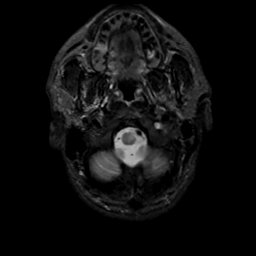

MR Study #13, May 19, 1991 -- Slice #3

[Home][Help][Clinical][Tour 1][Tour 2] Slice 3